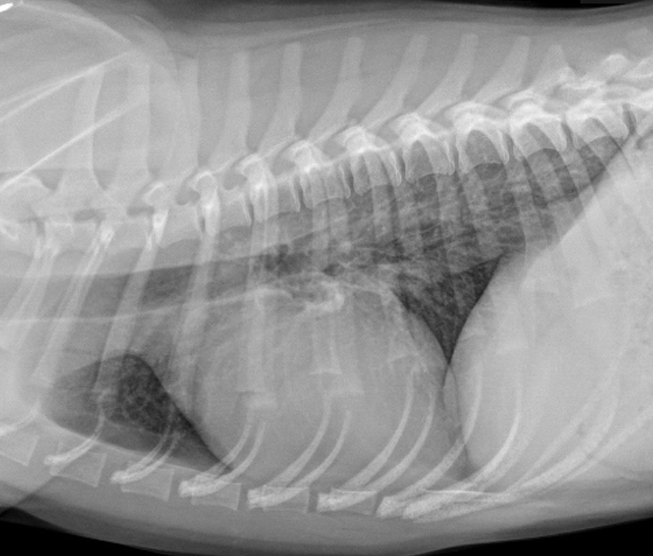

Interstitial pattern

aorta and vena cava is blurry